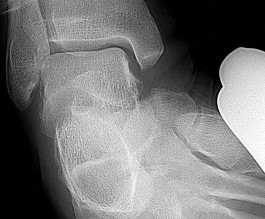

Question 9

A 30-year-old athlete sustains a hyperplantarflexion injury to his midfoot. Weight-bearing radiographs show 3mm of widening between the medial and middle cuneiforms. What is the primary stabilizing structure of the Lisfranc joint complex?

Explanation

The Lisfranc ligament is an intra-articular ligament that connects the lateral aspect of the medial cuneiform to the medial base of the second metatarsal. It is the strongest and primary stabilizer of the Lisfranc joint complex. The dorsal ligaments are relatively weak, predisposing the joint to dorsal dislocation during hyperplantarflexion.